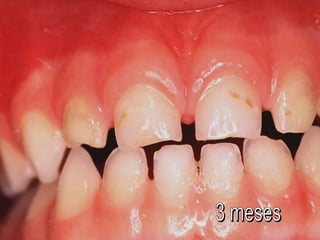

Las primeras lesiones no son cavitadas

a medida que pasan los años

aparecen más lesiones cavitadas